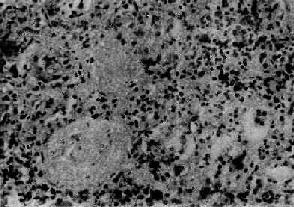

图12-22弥漫性硬化性肾小球肾炎 肾小球纤维化,玻璃样变;肾小管也大部分萎缩纤维化;间质纤维组织增生,有多数慢性炎细胞浸润

十、弥漫性硬化性肾小球肾炎弥漫性硬化性肾小球肾炎(diffuse sclerosing glomerulonephritis)是各种类型肾小球肾炎发展到晚期的结果。大量肾小球纤维化、硬化,原始的病变类型已不能辨认。病人的主要症状为慢性肾功能衰竭。有些病人过去有肾炎的病史。约25%的病人起病缓慢,无自觉症状,无肾炎病史,发现时已为晚期。 【病理变化】 两侧肾对称性萎缩变小,色苍白,表面呈弥漫性细颗粒状。有时可有散在的小囊肿形成。肾不而质硬,故称颗粒性固缩肾。切面见肾皮质萎缩变薄,纹理模糊不清,皮髓质分界不明显。肾盂周围脂肪组织增多。小动脉壁增厚,变硬,口哆开。 镜下可见大量肾小球纤维化及玻璃样变,有的形成无结构的玻璃样小团(图12-22)。这些肾小球所属的肾小管也萎缩、纤维化、消失。纤维组织收缩,使纤维化、玻璃样变的肾小球相互靠近集中(图12-23)。有些纤维化的肾小球消失于增生的纤维结缔组织中。无法辨别原有的病变类型。存留的肾单位常发生代偿性肥大,肾小球体积增大,肾小管扩张。肾小管上皮细胞呈立方或高柱状,有些肾小管明显扩大呈小囊状,上皮细胞扁平。扩张的肾小管腔内常有各种管型。间质纤维组织明显增生,并有多数淋巴细胞和浆细胞浸润。由于肾组织缺血及高血压,间质内小动脉硬化,管壁增厚,管腔狭小。